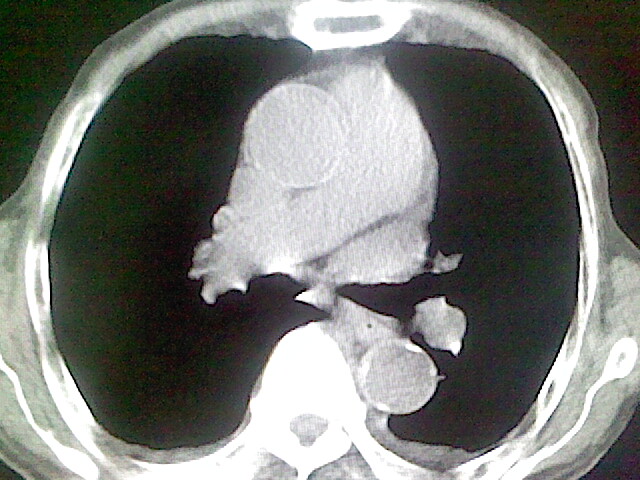

以下是引用zsl6918在2008-8-28 16:49:00的发言:[br]双肺炎性病灶,食管狭窄估计与心房增大压迫所致。

以下是引用xulianj在2008-8-28 20:36:00的发言:[br]慢支肺气肿伴感染,右上肺陈旧性结核;食道建议胃镜检查。

以下是引用wqs571018在2008-8-28 21:18:00的发言:[br]慢支继发感染,右上肺陈旧性结核;食道建议胃镜检查。